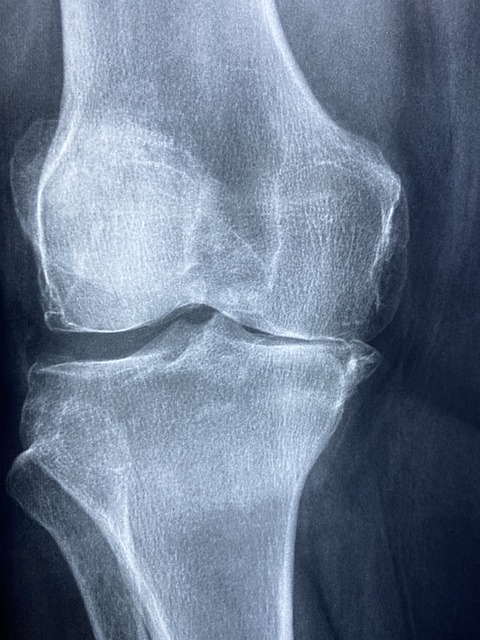

퇴행성 관절염은 관절의 연골이 서서히 손상되어 발생하는 만성적인 질환으로, 주로 노인이나 중년에 많이 발생합니다.

□ 통증 : 가장 흔한 증상으로 관절이 닳아서 생기는 통증입니다. 이 통증은 활동으로 인해 악화되며, 휴식을 취하면 완화되기도 합니다.

□ 움직임의 제한 : 관절의 변형이나 통증으로 인해 움직임이 제한될 수 있습니다. 이로 인해 일상생활에 불편함을 경험하게 됩니다.

퇴행성 관절염의 치료는 증상의 완화, 기능 손상의 최소화, 그리고 생활 품질의 향상에 초점을 두고 있습니다. 비스테로이드계 항염증제(NSAIDs), 코르티코스테로이드 주사, 통증 완화제 등 다양한 약물 치료가 있습니다. 또한, 물리 치료나 운동 치료를 통해 근육을 강화하고 관절의 유연성을 유지할 수 있습니다. 심한 경우에는 수술적 치료를 고려할 수도 있습니다.